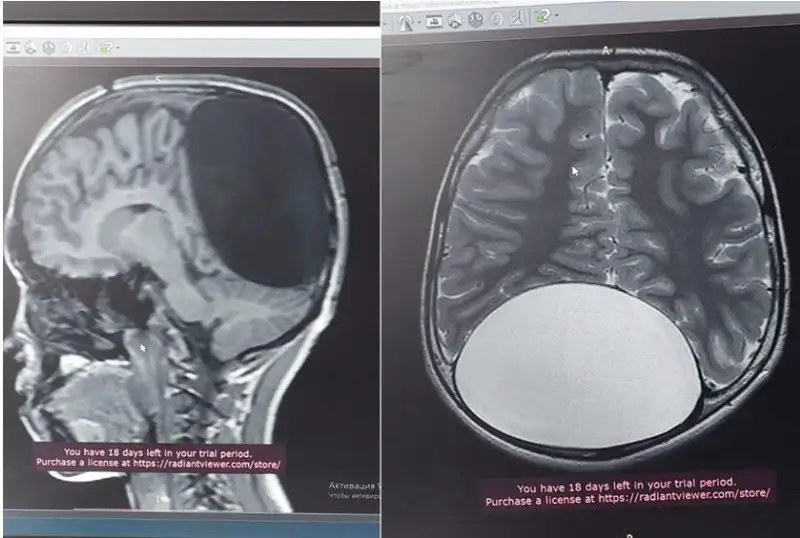

شىمكەنتتىك دارىگەرلەر 10 جاسار بالانىڭ ميىنان ءبىر ۋىس قۇرت الدى